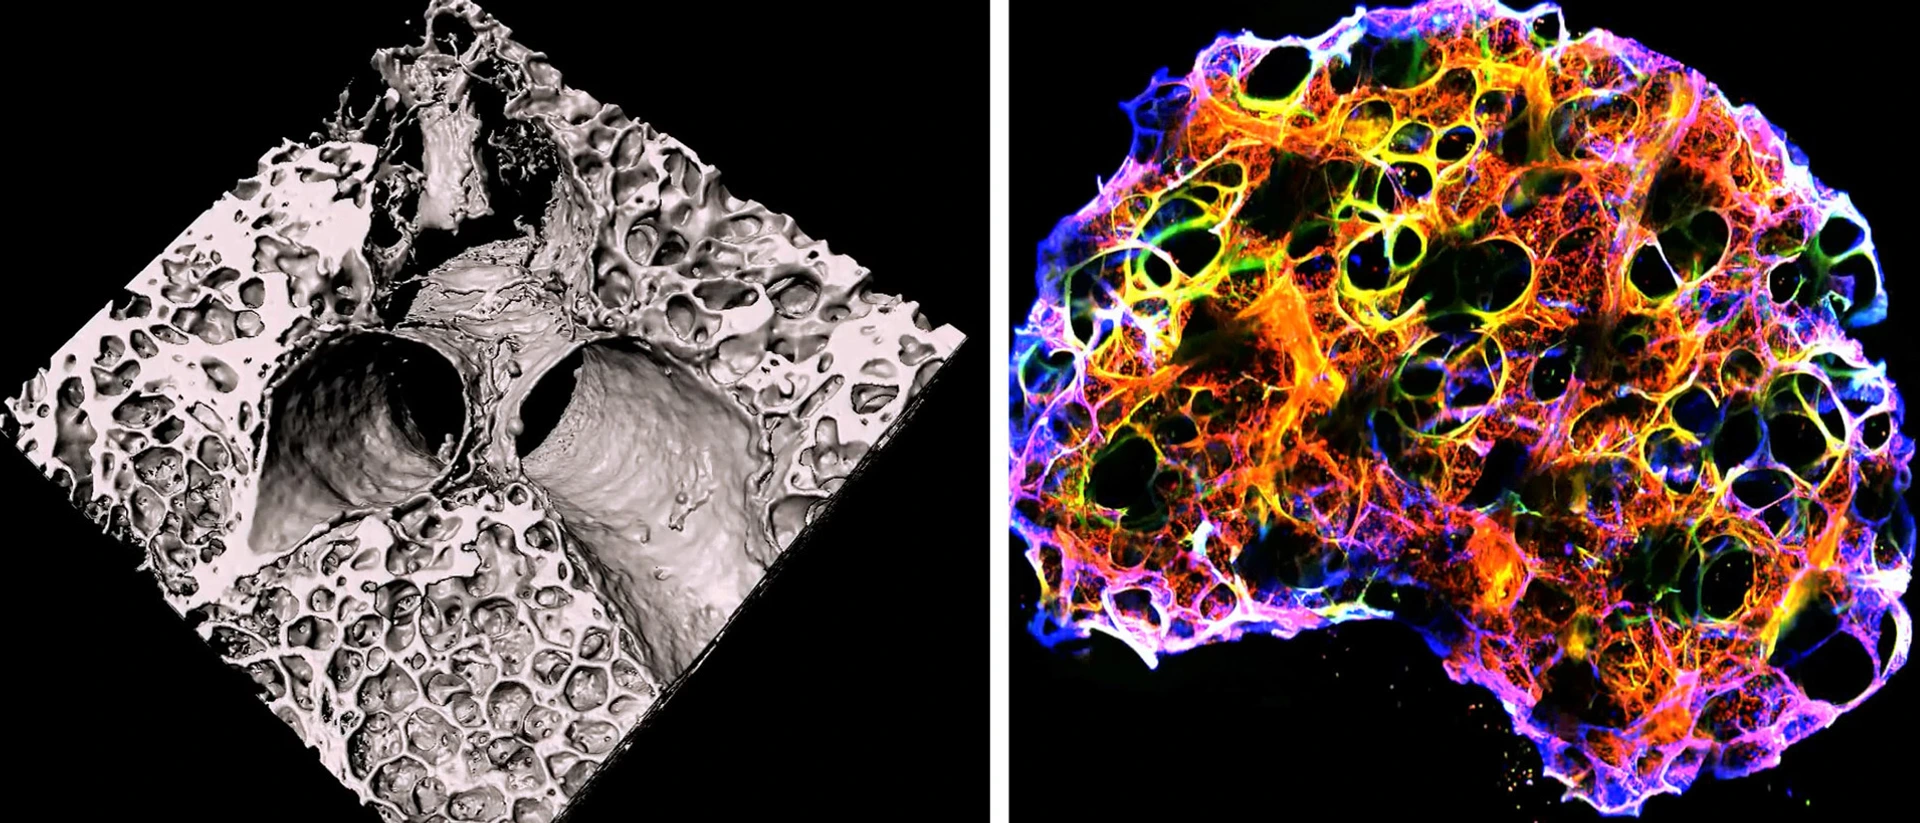

Many environmentally triggered lung diseases are still considered incurable. We explore the immunological mechanisms underlying chronic lung diseases such as COPD, lung fibrosis, asthma, lung cancer and the complications following lung transplantation. We want to translate our findings into preventative and therapeutic approaches for patients.

Many environmentally triggered lung diseases are still considered incurable. We at the Institute of Lung Health and Immunity (LHI) explore the immunological mechanisms underlying chronic lung diseases such as COPD, lung fibrosis, asthma, lung cancer and the complications following lung transplantation. We want to translate our findings into preventative and therapeutic approaches for patients.